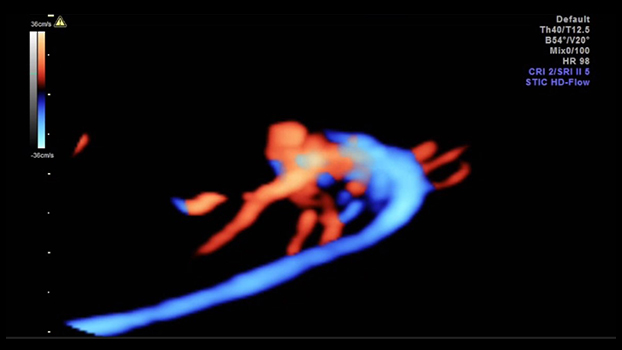

Quest’esame viene riservato solo alle pazienti che hanno una precisa indicazione medica (cardiopatie pregresse, translucenza patologica, diabete scompensato, sospetti di malformazioni evidenziate durante l’ecografia del secondo trimestre ecc.) Viene esaminata con estrema attenzione l’ anatomia del cuore e dei grossi vasi, la continenza delle valvole, l’integrità dei setti ed i ritorni venosi, la velocità di picco della aorta, dell’arteria polmonare e del dotto arterioso. Si valuta inoltre il flusso del sangue che proviene dalla placenta attraverso il dotto venoso.